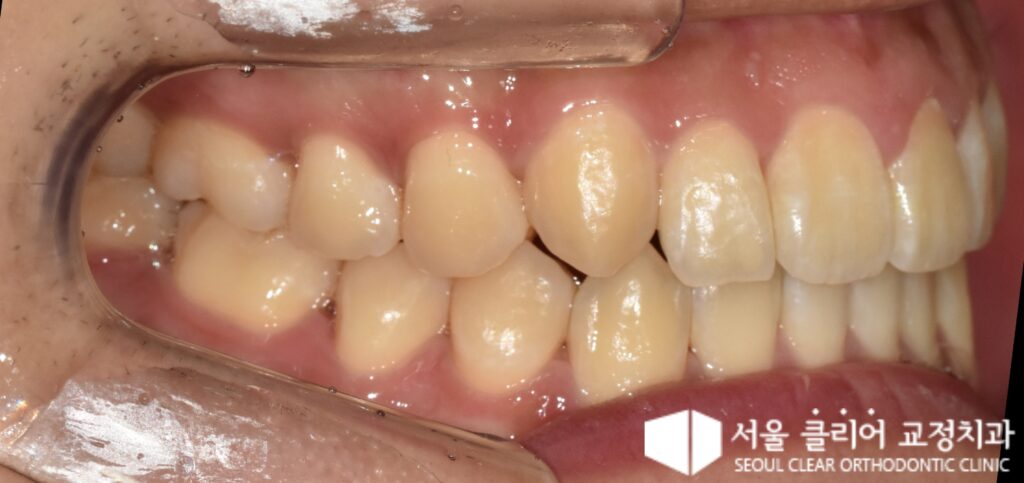

환자분의 초기 구강 사진을 살펴보면 여러 가지 복합적인 문제점들이 관찰되었습니다.

- 정중치아 벌어짐 (Diastema): 위 앞니 사이에 뚜렷한 공간이 벌어져 있어 심미적으로 불만족스러운 상태였습니다.

- 송곳니 덧니: 위쪽 어금니들이 전방으로 이동하면서 전체적으로 치아가 배열될 공간이 부족해졌습니다. 이로 인해 위 송곳니가 제 위치를 찾지 못하고 잇몸 위쪽으로 솟아오른 형태로 배열되었습니다.

- 아래턱 비대칭: 아래턱의 비대칭으로 인하여 아래 치열의 정중선(가운데 선)이 사진 기준 우측으로 크게 치우쳐 있었습니다.